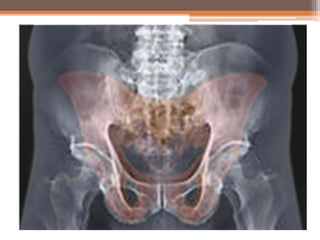

Trefoil Pelvis